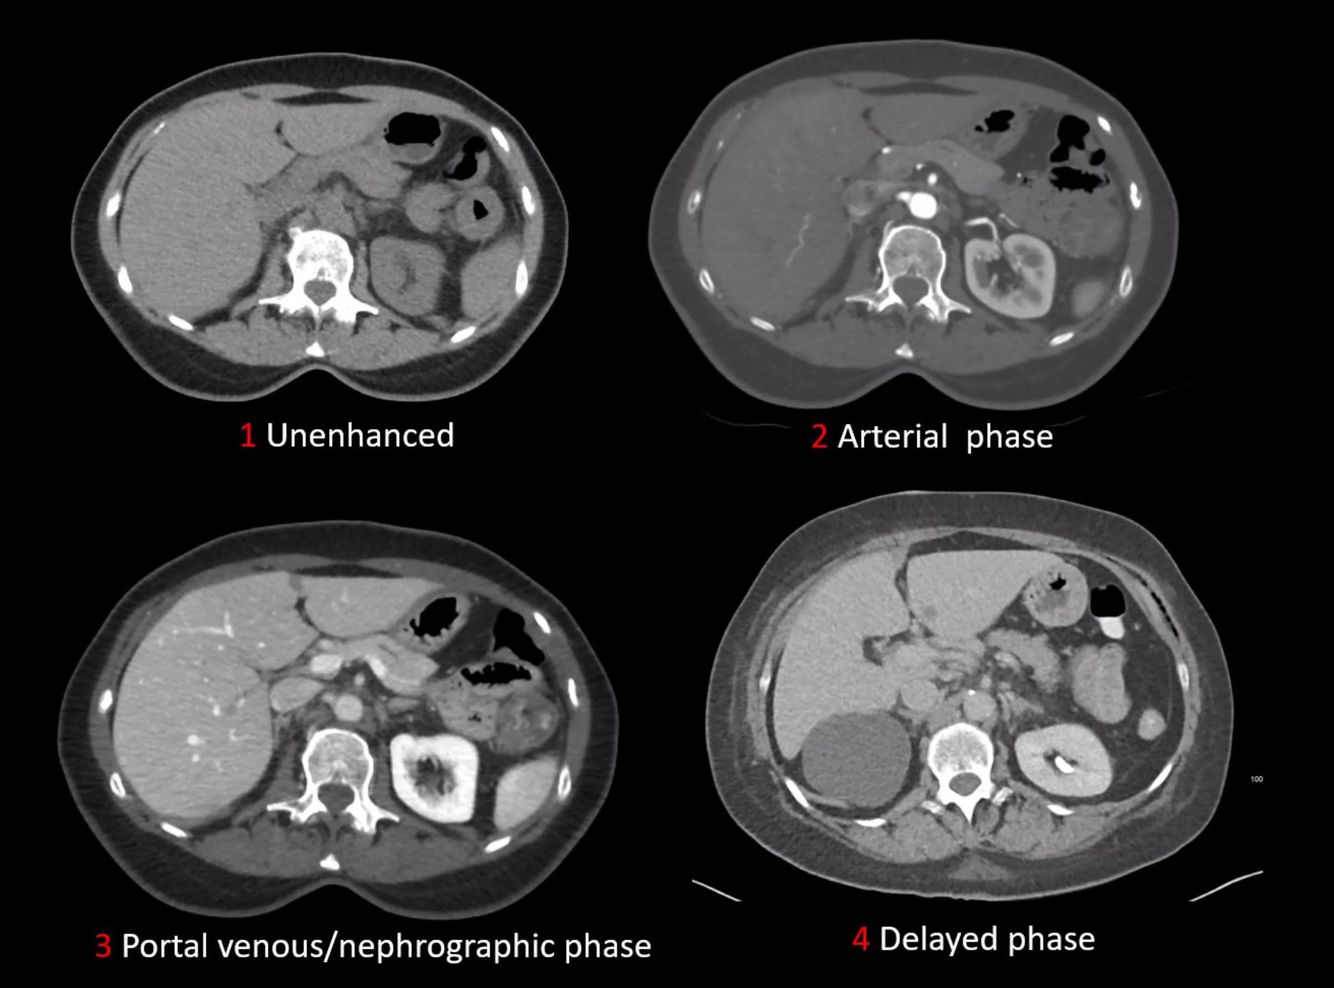

CT contrast phases